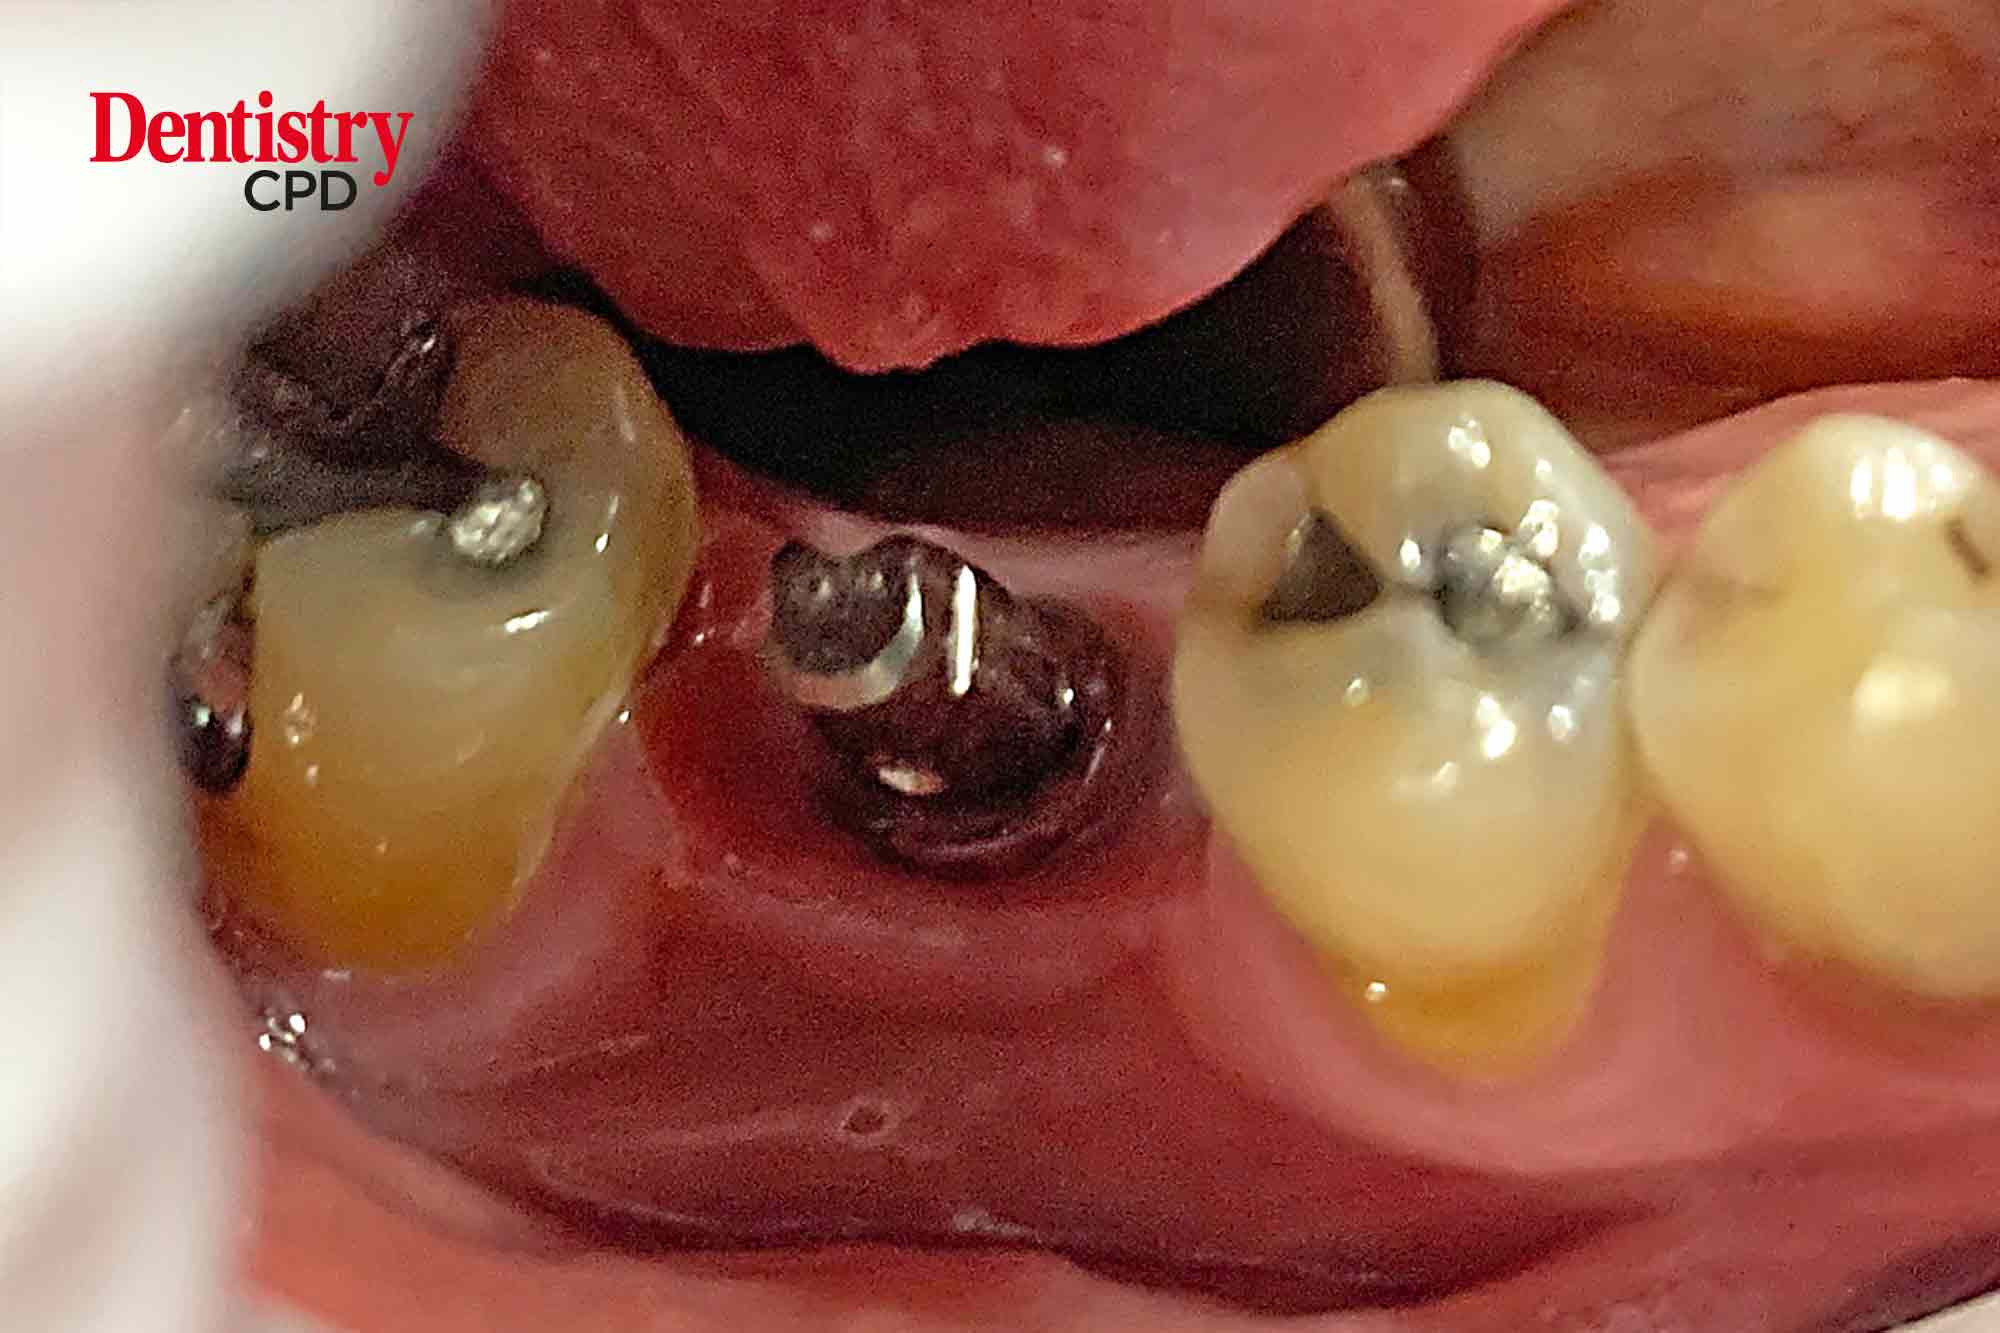

Senthil Thiagarajan describes decontamination of the implant surface and surrounding tissue for a patient suffering from peri-implantitis

To present a case study that describes decontamination of the implant surface and surrounding tissue for a patient suffering from peri-implantitis.